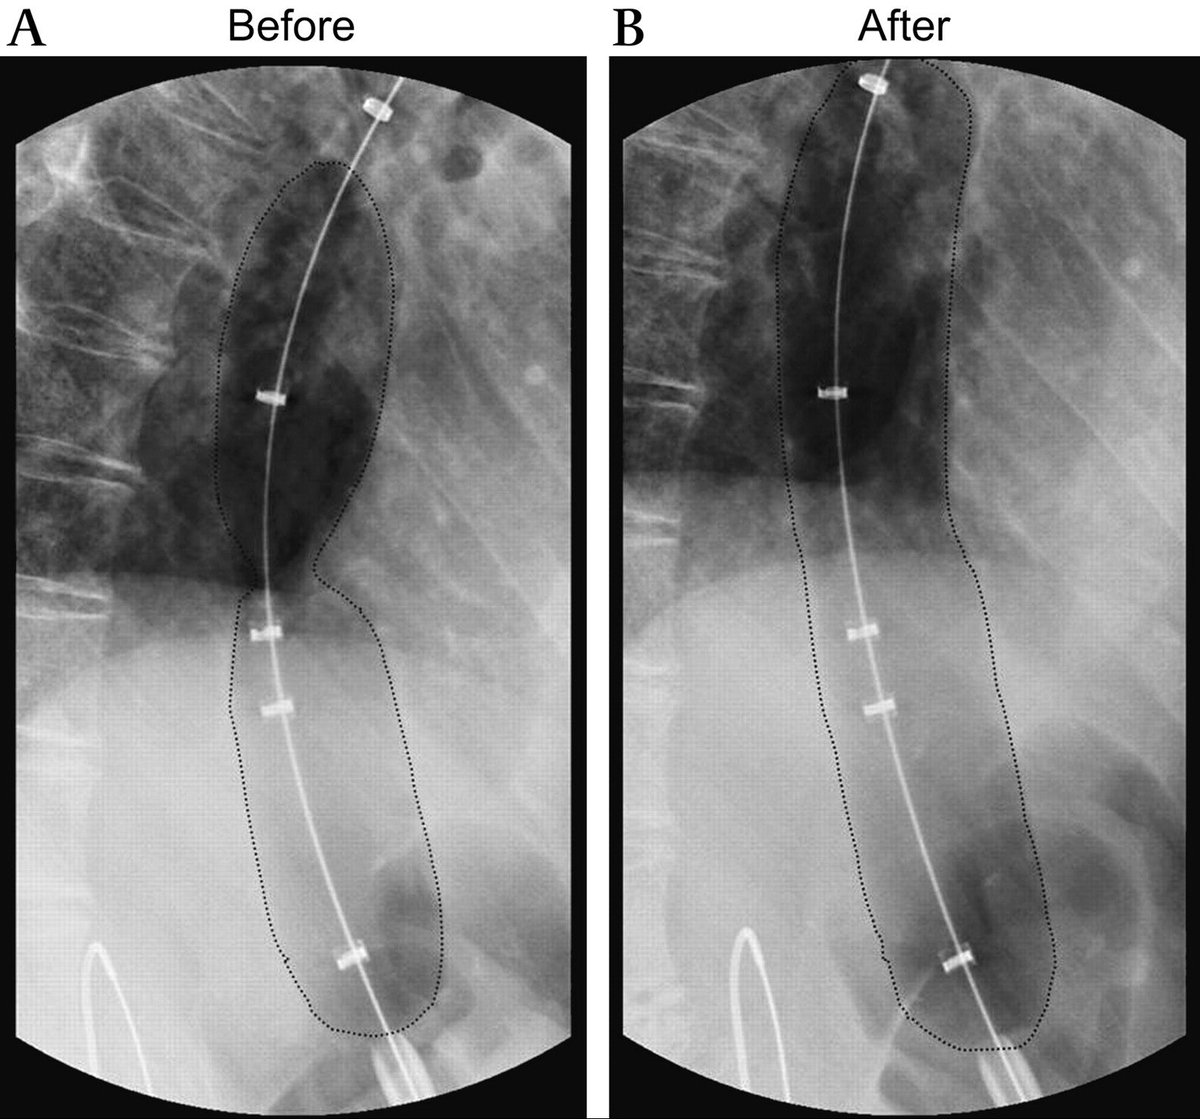

يمكن علاج المشكلة بطرق جراحية او تداخلية و اخرى غير جراحية. من الطرق غير الجراحية: توسعة الصمام السفلي للمريء بواسطة المنظار عن طريق البالون ل ٣٠، ٣٥، ثم ٤٠ ملم ان استدعى الامر. ثلث الاشخاص الذين يتم علاجهم بهذه الطريقة قد يحتاجون الى اعادتها مرة اخرى خلال ٥ سنوات

هذه صور لاحدى الحالات التي اجريت في المستشفى الجامعي و التي بحمد الله تكللت بالنجاح بواسطة المنظار عن طريق اجراء فتحة صغيرة لا تتجاوز ٢ سم في المريء.